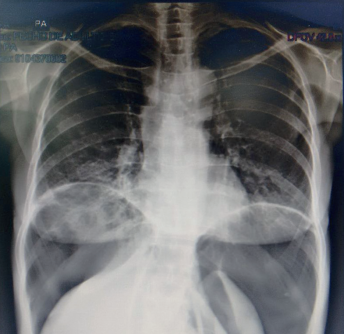

En los exámenes de laboratorio se encontró función renal y hepática normales, no había leucocitosis ni neutrofilia, la albúmina sérica fue de 3,5 g/dl y el VIH fue negativo. En las radiografías de tórax y de abdomen en posición vertical, se observó una gran cámara de neumoperitoneo que desplazaba el hígado y el bazo hacia abajo.

Al no encontrarse signos de irritación peritoneal, se practicó una tomografía toraco-abdominal en la que se observó: derrame pleural bilateral con engrosamiento de las cisuras, bronquiectasias basales bilaterales, atelectasia parcial de ambos lóbulos inferiores, notoria distensión del esófago con sonda en su interior, hidroneumoperitoneo, abundante líquido libre en la cavidad abdominal y distensión de las asas intestinales (figuras 1,2,3).